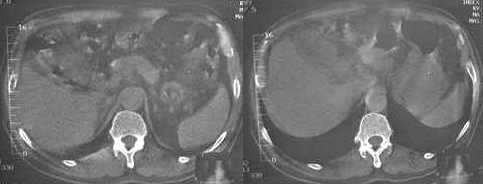

男,60岁,反复头痛,头昏,测血压最高240/120

临床怀疑嗜镉细胞瘤。做ct想了解肾上腺有无肿块。

3. 1167 1168 图 胆囊壁旁是什么结构?似乎不是胆囊壁增厚

胆囊旁、肝脏前缘为运动伪影。胃内后方考虑肠管,建议此类检查前喝0.7%泛影葡安800ml后再扫描。